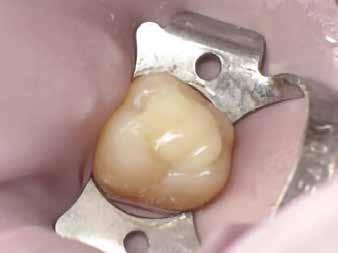

2. ábra: A páciens egy nem megfelelő I. osztályú ezüstamalgám töméssel és II. osztályú szuvasodással jelentkezett. A fog izolálása kofferdám alkalmazásával történt.

3. ábra: A preparálás, a bondozás és a kompozit felvitele után. (Megjegyzés: némi kompozit túlfolyás látható a mesiális doboz axiális falain).